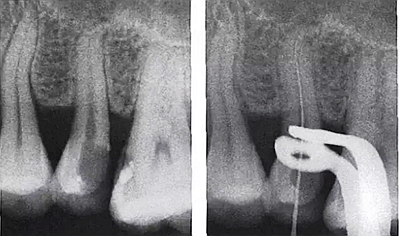

3.根管內(nèi)出現(xiàn)明顯的側(cè)支根管時。

解決:會通過側(cè)枝根管形成短路,當(dāng)銼針到達側(cè)枝根管口試即提示到達或超出根尖。

需結(jié)合X光片共同確認(rèn)!

5.用X線片輔助確認(rèn)

1.進入側(cè)枝根管

1.根管銼重新向根尖孔靠近,直至信號正常